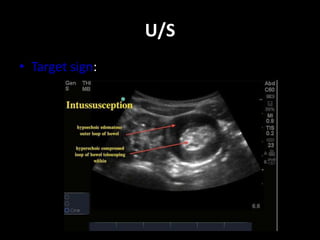

U/S

• Target sign: